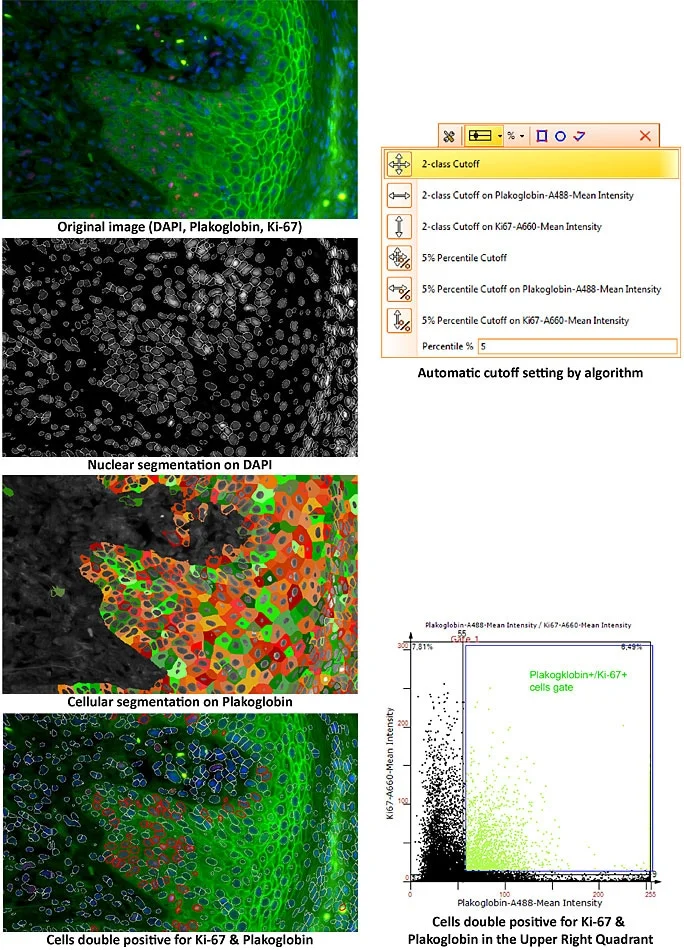

Revolutionizing Tissue Analysis: Image-Based Cytometry

Image-based cytometry is transforming tissue analysis by combining microscopy with flow cytometry features. It enables rapid, automated characterization of cells in their native environment, advancing pathology, oncology, and precision medicine with AI integration.

Multiplexing Techniques as Useful Tools for High-Content Phenotyping

Multiplexing enables high-content phenotyping by analyzing multiple markers in a single tissue section. Combined with TissueFAXS CHROMA and StrataQuest Apps, it delivers detailed insights into tumor microenvironments and complex cellular interactions.